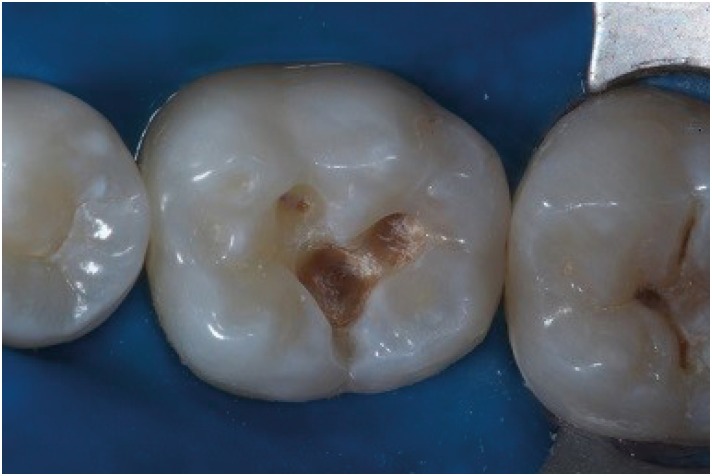

Figure 4

After phosphoric acid and adhesive layer placed, Bulk Fill composite resin as placed in the cavity with one increment.

rde-45-e9-g004.jpg

Figure 5

Matrix placed in the occlusal surface.

rde-45-e9-g005.jpg